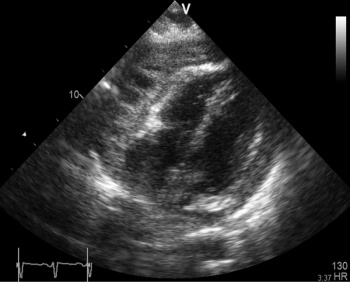

Figure 4: Subcostal view showing a thick exudative pericardial effusion. Thick fibrinous strands can be seen crossing the space and tethering the myocardium to the pericardium

Figure 4: Subcostal view showing a thick exudative pericardial effusion. Thick fibrinous strands can be seen crossing the space and tethering the myocardium to the pericardium(click to enlarge)

Surprisingly the echocardiogram showed a large pericardial effusion containing thick viscid heterogenous fibrin rich exudate with evidence of septation loculation, and organisation, indicating that these changes were not acute. There was Doppler evidence of pericardial constriction; however, the absence of bi-atrial enlargement suggested that it might be fairly recent.

LV and RV function were moderately impaired with EF of 30-40% due to a combination of adhesion and tethering and constriction, hence the compensatory tachycardia to maintain cardiac output.